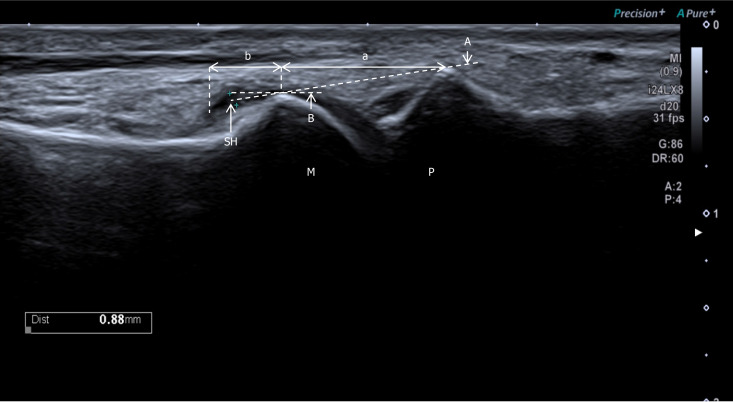

Methods: This cross-sectional study included 56 patients (112 MTPJs) with T2DM from Shenzhen Traditional Chinese Medicine Hospital. Synovial hypertrophy was evaluated using a refined semi-quantitative ultrasound grading system focusing on the dorsal recess overlying the metatarsal bone. Serum 25(OH)D levels were measured. Logistic regression and threshold analyses assessed associations between vitamin D status and hypertrophy severity.